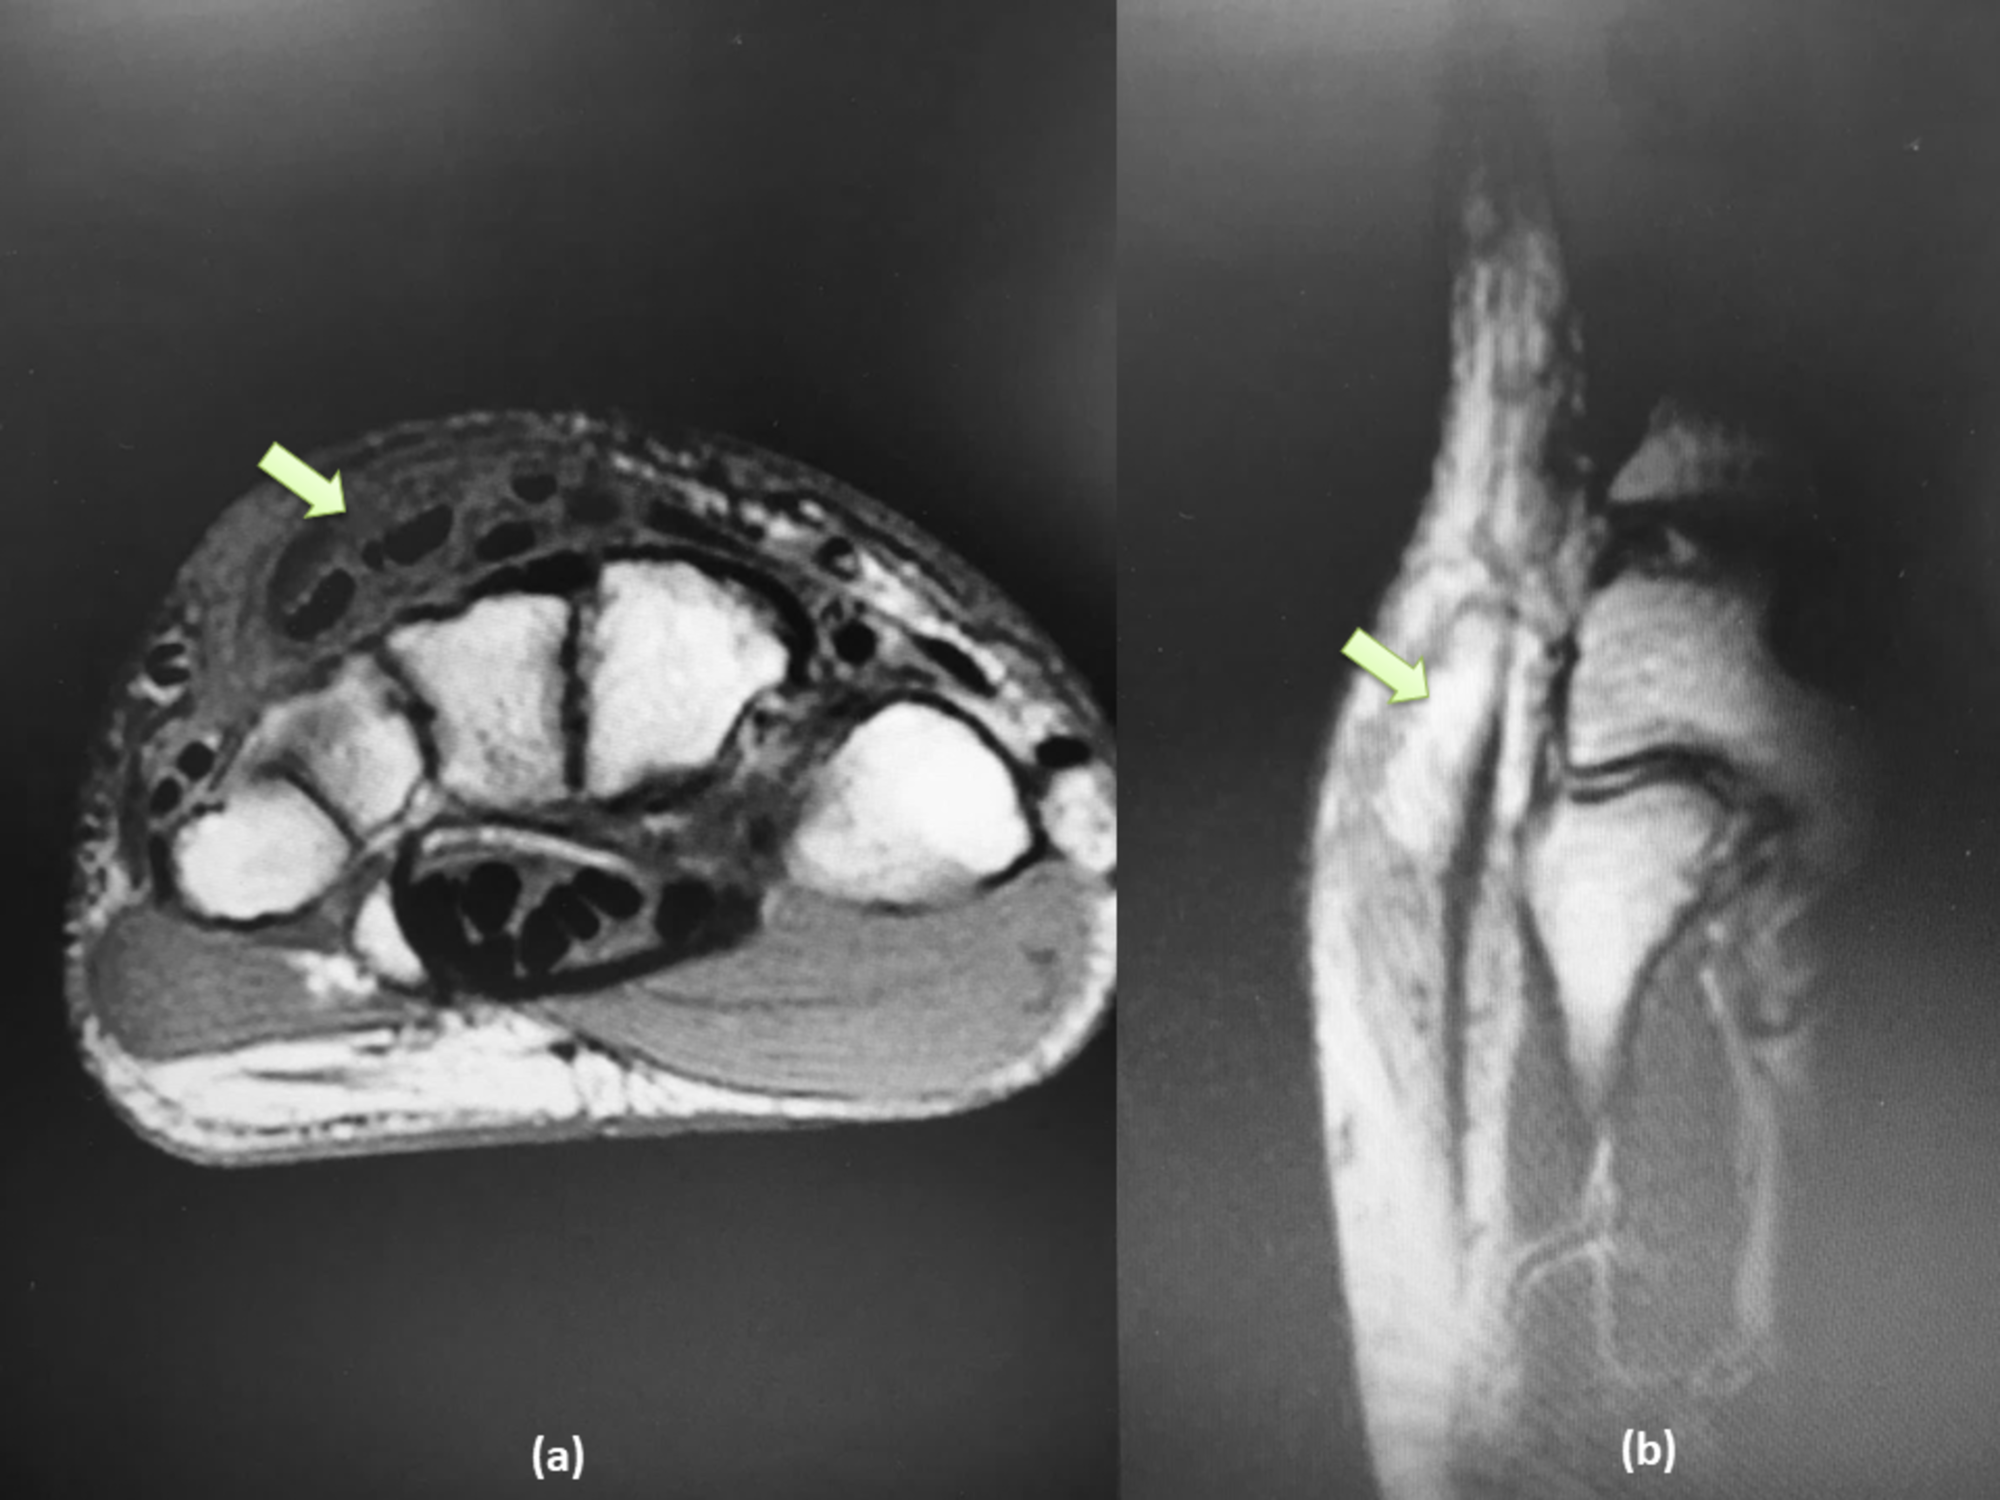

Fourth extensor compartment tenosynovitis Image Extensor Compartments Mri Adjacent subcutaneous edema is present. They are located on the posterior aspect. Mri findings include isolated tenosynovitis of the 4th extensor compartment, most severe distal to the er. De quervain tenosynovitis, also known as washerwoman's sprain/strain, is a painful stenosing tenosynovitis involving the first extensor (dorsal) tendon compartment. We review the anatomy and normal mri appearance of the clinically important. Extensor Compartments Mri.